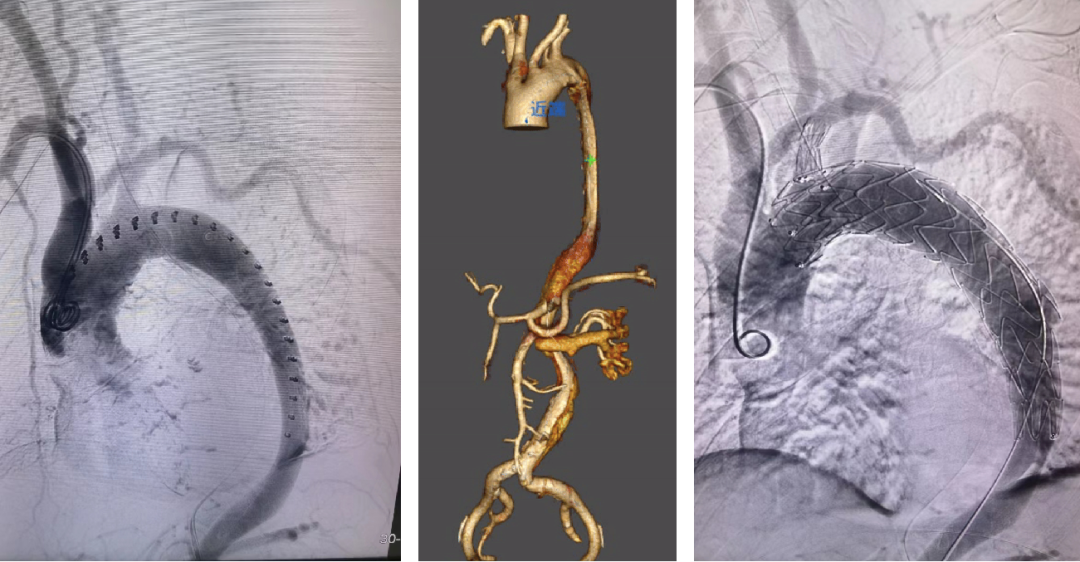

★Case 2 穿透性溃疡,右位弓

治疗难点:右位弓,锚定区不足、四分支走行变异,LSA重度狭窄

治疗目的:重塑主动脉形态,保障弓上四支变异分支血管正常供血

手术策略:TEVAR+烟囱(右锁骨下动脉)+潜望镜(左锁骨下动脉)

结果:四支血管血运恢复,术后造影血流通畅

释放主体支架

建立左锁骨下轨道

建立潜望镜